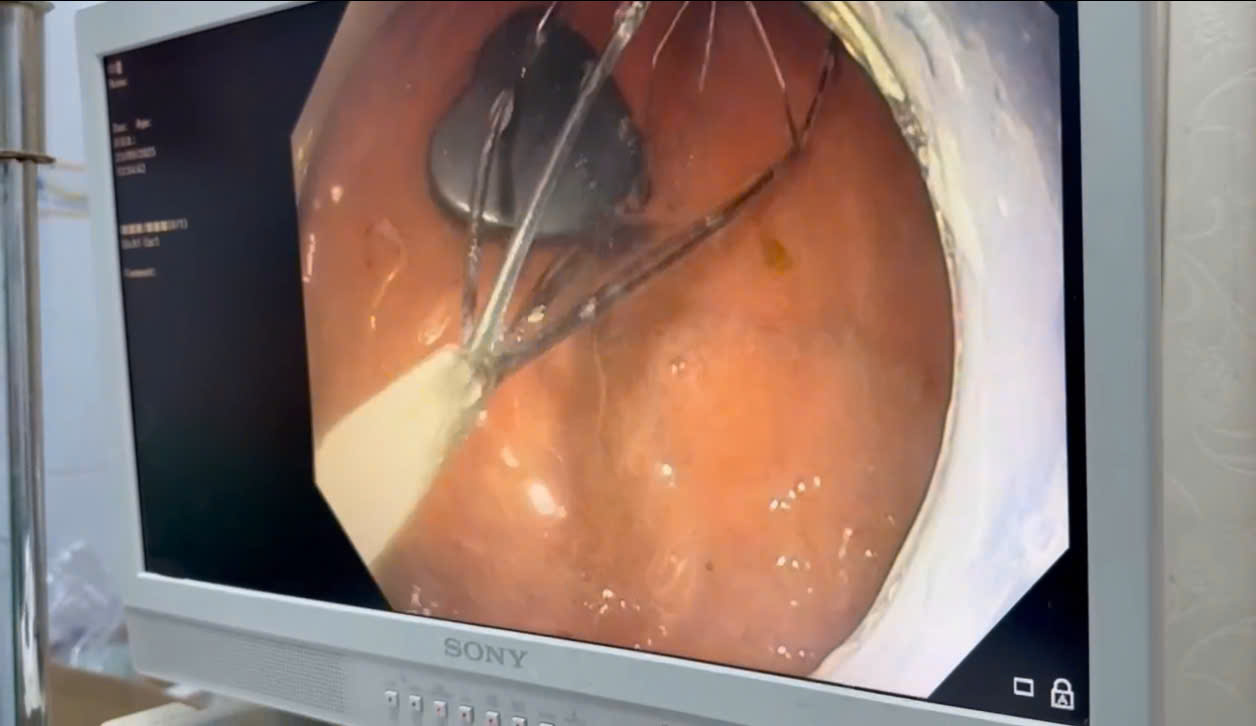

Ngay lập tức, bệnh nhi được chuyển đến Khoa Nội soi. Ekip bác sĩ tiến hành nội soi gây mê, sử dụng dụng cụ chuyên dụng để gắp dị vật. Sau một khoảng thời gian ngắn, cục nam châm đã được lấy ra an toàn. Kiểm tra đường tiêu hóa không ghi nhận tổn thương, bé tỉnh táo và được xuất viện trong ngày.

Hình ảnh dị vật nam châm hình trái tim được lấy ra